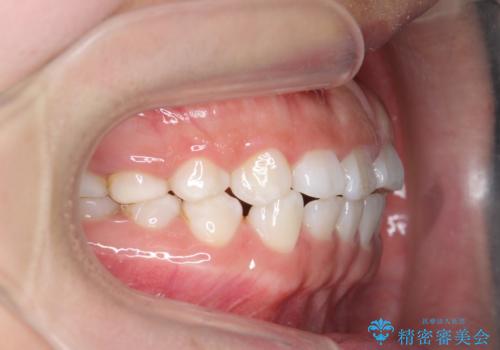

インビザライン 気になるすきっ歯の改善

- 上下顎前歯部の空隙が気になるので治したいと当院にいらっしゃった方の症例です。

非抜歯、インビザラインによる矯正治療により歯と歯の隙間および前歯の上下の隙間を閉じ切りました。